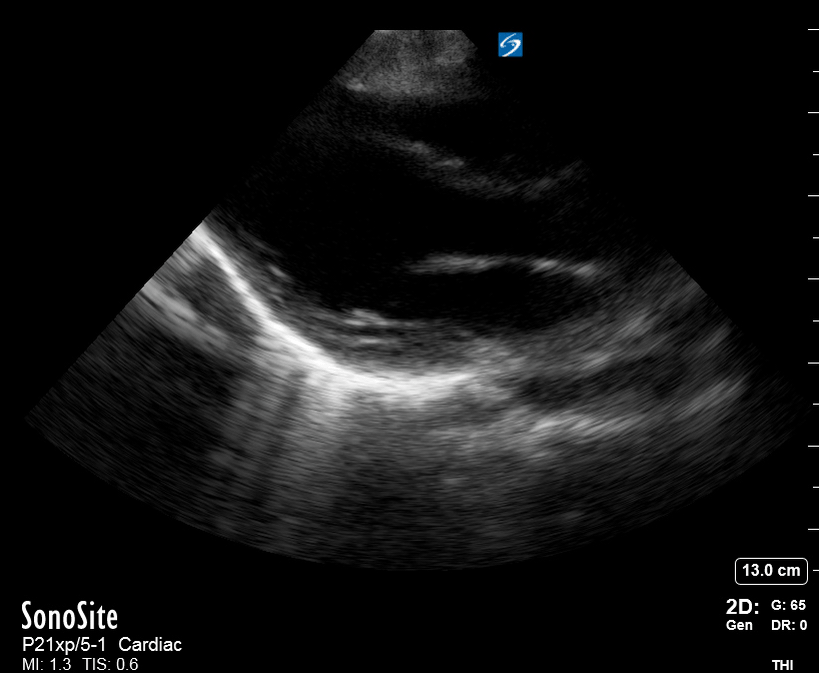

THE VIEWS

The A4C view provides an accurate chamber size comparison. However, achieving a proper A4C view (avoiding foreshortening or ballooning, and visualising the four chambers with a vertically oriented interventricular septum) can be a challenging exercise of image acquisition. Additionally, the PSAX view at the level of the papillary muscles shows both LV and RV side by side and is useful to assess function and size. When RV pressure is high, the septum will be pushed and flattened towards the LV, resulting in the characteristic “D-shaped” LV or “D sign”.

PITFALLS

When comparing size, beware of correct image acquisition, as oblique planes lead to misinterpreting the RV:LV ratio. For apical views be sure to slide the probe sufficiently laterally on the chest wall so that it lies over the true apex. Also, be sure to obtain a real horizontal plane, avoiding foreshortening (ballooning). For the PLAX view it is useful to fan through the heart’s long axis, making sure that LV visualization is maximized relative to the RV. Furthermore, an understanding of probe placement and marker orientation conventions is fundamental. If inadvertently scanning in reverse orientation, the normally larger LV could be mistaken for an abnormally enlarged RV.